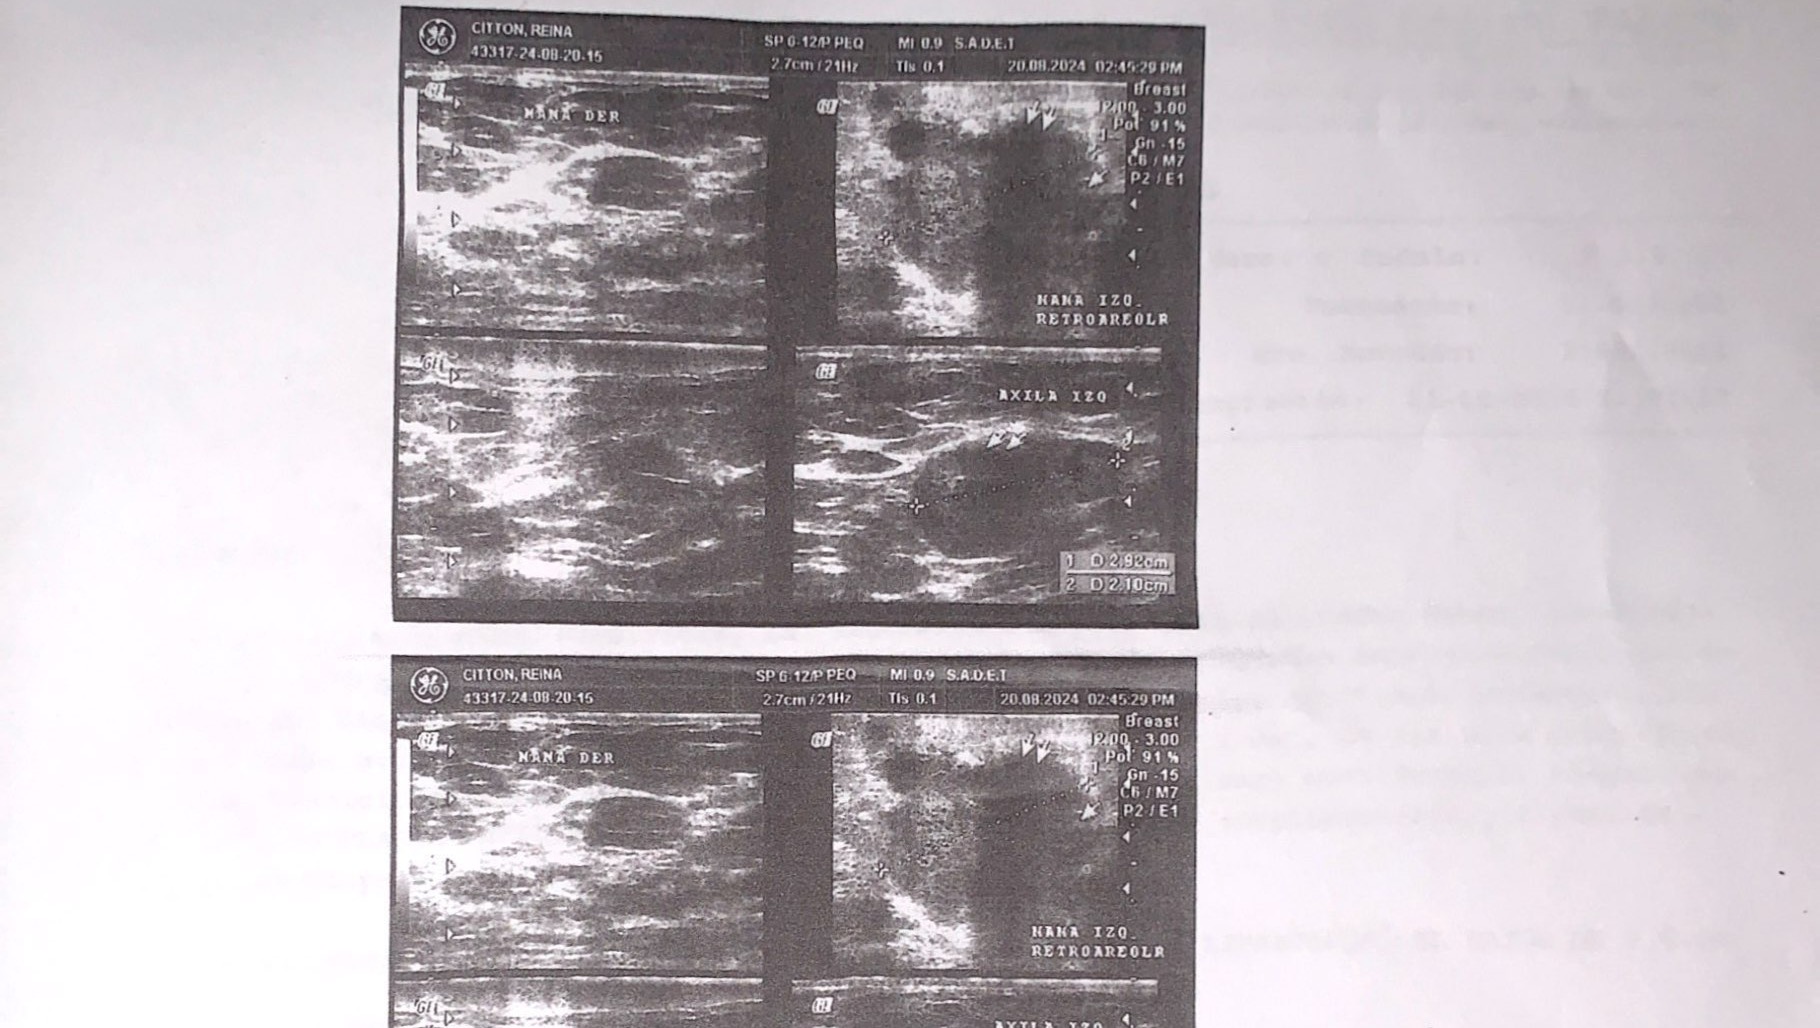

Ayudemos con el Cancer de Mama a mi tia Reina Citton

Hola mi nombre es Maritza, por este medio me dirijo a ustedes para la colaboración del tratamiento de mi tía mamá, que lamentablemente fue diagnosticada de CARCINOMA DUCTAL INFILTRANTE DE MAMA IZQUIERDA (cancer de mama), el cuál se encuentra muy avanzado y se requiere de un tratamiento que consta

de mucho cuidado y requiere medicina muy costosa por eso estoy acá representando mi familia para poder costear este duro proceso les agradezco su colaboración y atención prestada .